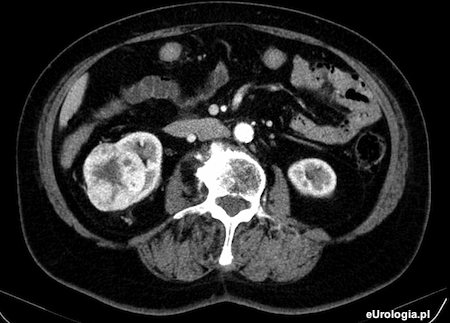

Nefrektomia jest leczeniem z wyboru u pacjentów z guzem, który w badaniu tomograficznym sugeruje zmianę złośliwą. Najczęściej stwierdzanymi zmianami w obrębie guza są wzmożony przepływ krwi, patologiczne unaczynienie i rozpad wewnątrz guza. Nefrektomia jest dużym zabiegiem onkologicznym, który wymaga szczegółowego przygotowania przed operacją. Pacjent kwalifikowany jest do operacji przez anestezjologa - lekarza, który odpowiada za znieczulenie pacjenta. W dniu poprzedzającym zabieg obowiązuje dieta ścisła z ograniczeniem wypijanych płynów na noc. Rano przed operacją brzuch pacjenta jest golony jednorazową maszynką przez pielęgniarkę.

Fot. Skan z tomografii komputerowej przedstawiający 8 cm guz prawej nerki